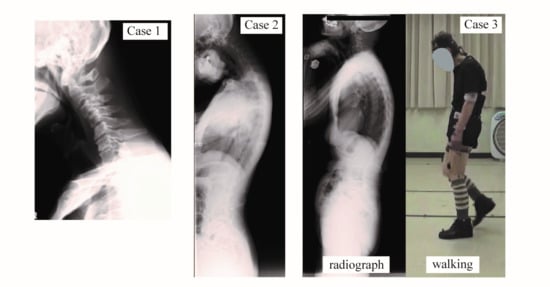

| Case | Case 1 | Case 2 | Case 3 |

|---|---|---|---|

| Age (y) | 75 | 66 | 81 |

| Sex | M | M | F |

| Height (cm) | 169 | 162 | 145 |

| Weight (kg) | 60 | 49 | 37 |

| Head-C7 SVA (mm) | +115 | +117 | +8.2 |

| Cervical Kyphosis | 40° | 37° | 0.3° |

| T1 slope | 39° | 0° | 11° |

| C7 SVA (mm) | −21 | −64 | 4.9 |

| Lumbar Lordosis | 40° | 63° | 28° |

| Number of HAL sessions | 10 | 10 | 10 |

| Frequency of HAL sessions | (1st) 5/week (2nd) 1/month | 1/week | 1/2–3 weeks |

| Duration of HAL sessions | (1st) 2 weeks (2nd) 10 months | 10 weeks | 6 months |